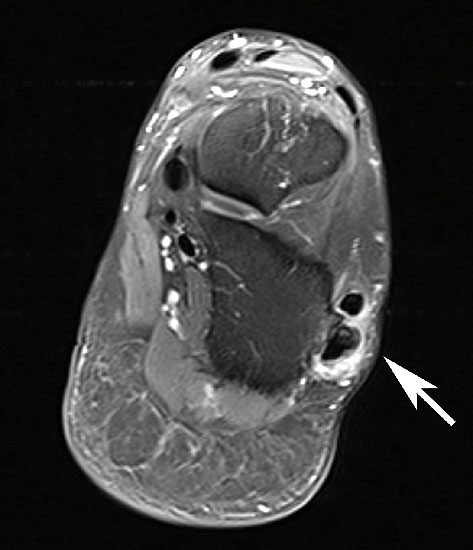

Unterbrechung des Retinakulums als indirektes Zeichen einer traumatischen Peronealsehnenluxation im MRT.

Abbildung 6

Neben der klinischen Untersuchung besitzt in der Diagnostik von Sehnenpathologie das MRT mit Kontrastmittel einen hohen Stellenwert 8910. Kontrastmittelaufnahme in die Sehne ist immer als Hinweis auf einen Riss zu werten. Weiterhin ist Flüssigkeit im Sehnengleitlager oder die Aufnahme von Kontrastmittel in das Sehnengleitgewebe ein indirektes Zeichen einer Sehnenpathologie.